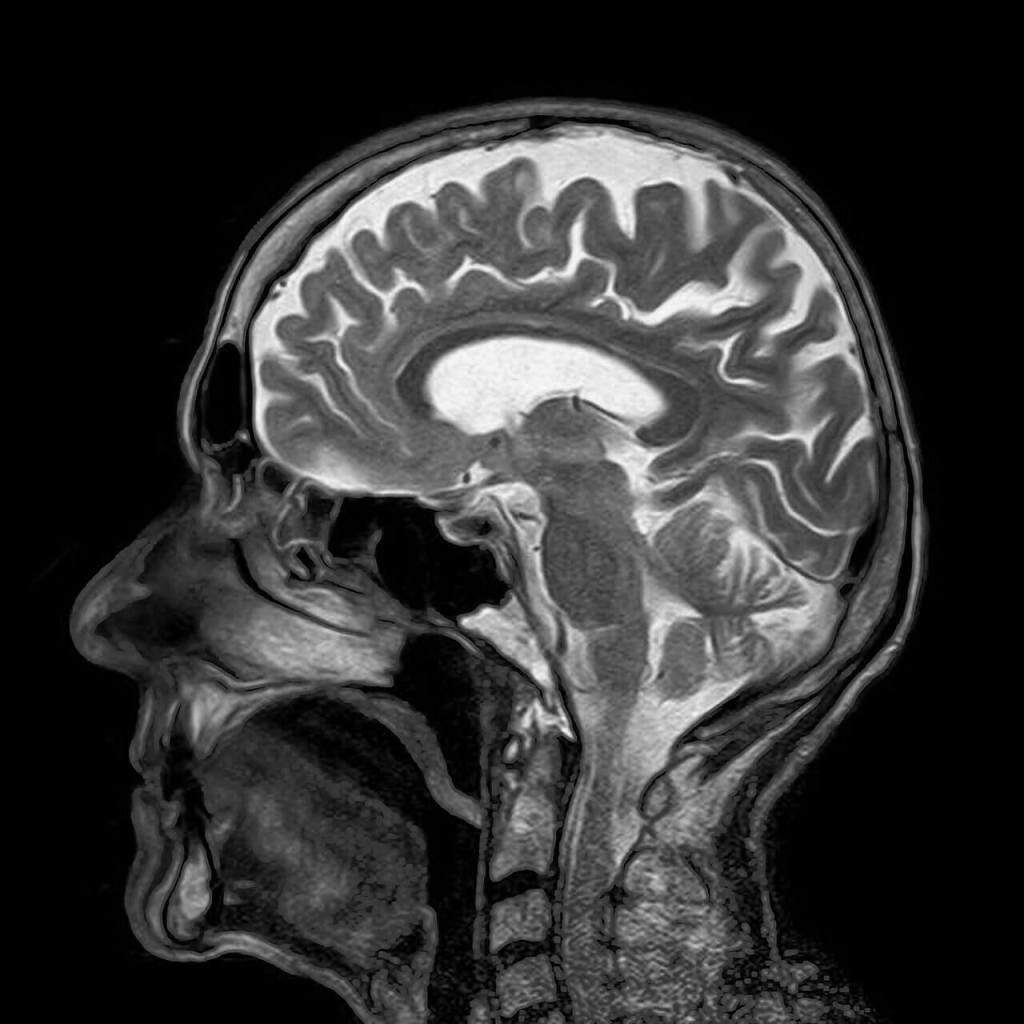

Osnabrück es una hermosa ciudad alemana de Baja Sajonia, famosa por acoger la firma de la Paz de Westfalia que puso fin a la guerra de los 30 años. Visité la ciudad por primera vez en diciembre de 2005, coincidiendo con el tradicional mercado navideño de la ciudad, invitado a participar en un seminario organizado en la Universidad de Osnabrück. La universidad me alojó en el conocido hotel Walhalla, que se enorgullecía de aparecer reflejado en una de las obras del famoso escritor Erich Maria Remarque, natural de Osnabrück y autor de la gran novela pacifista Sin novedad en el frente. Al llegar al hotel coincidí con otro de los participantes en el seminario, el profesor Ian R. Young, un físico británico de gesto muy adusto, profesor de radiología en el Imperial College of Science, Technology and Medicine de Londres. Entonces no lo sabía, pero el profesor Young era todo un pionero de la ciencia, había sido el artífice de la obtención por primera vez en la historia de la imagen por resonancia magnética de un cerebro humano en 1978. Más de cuarenta años después de ese gran logro, la técnica de imagen médica por resonancia magnética se ha convertido en una de las más valiosas herramientas de diagnóstico médico de que disponemos hoy en día, y al igual que sucede con otros muchos avances tecnológicos de los que disfrutamos, sus fundamentos físicos se basan en un fenómeno de naturaleza cuántica.

La RMN es una de las principales técnicas de obtención de imagen médica junto con la ecografía por ultrasonidos, la tomografía axial computarizada, o TAC, y la tomografía por emisión de positrones, o PET, por sus siglas en inglés (Positron Emission Tomography). De entre todas estas técnicas, la RMN y la TAC son las que ofrecen mejor resolución de imagen (hasta un milímetro), aunque en la imagen de TAC se realzan los tejidos duros, como el hueso, mientras que en la RMN el contraste se produce para los tejidos blandos. La principal diferencia entre ambas técnicas es que en la TAC se hace uso de radiaciones ionizantes (rayos X) y, en cambio, en la RMN se emplea radiofrecuencia, que es una radiación no ionizante, lo que hace que la RMN carezca de los riesgos asociados a exposiciones prolongadas que sí presenta la TAC. No obstante, la RMN presenta ciertos inconvenientes frete a la TAC. Los principales son el intenso ruido que genera el sistema, que puede resultar incómodo para el paciente, y un intervalo de tiempo mayor para la exploración y la adquisición de las imágenes, de decenas de minutos o incluso una hora en el caso de la RMN frente a solo algunos minutos en el caso de la TAC. Además de esto, la exploración por RMN puede producir claustrofobia en algunos pacientes debido a que el cilindro hueco en el que deben introducirse suele ser de mayor longitud que el del escáner de TAC. Algunos escáneres de RMN tratan de resolver este último inconveniente mediante el uso de una estructura abierta en forma de U que reemplaza al tubo, pero la calidad de la imagen en este tipo de escáneres es inferior.

La imagen médica por RMN se basa en el fenómeno de la RMN para el núcleo más abundante en el organismo humano, el núcleo de hidrógeno, ya que casi el 70 % de la masa de un cuerpo humano es agua y hay dos núcleos de hidrógeno en cada molécula de agua. La imagen médica por RMN es una técnica altamente sofisticada que combina el uso de sistemas de emisión de ondas de radiofrecuencia de gran potencia (del orden del kW) y de detección de señales de radiofrecuencia extremadamente débiles (las producidas por los núcleos de hidrógeno de los tejidos del paciente), con el uso de campos magnéticos estáticos muy intensos, desde 0,2 hasta 7 Teslas en aplicaciones clínicas, e incluso 9,4 Teslas en investigación en humanos y hasta 17,6 Teslas en el caso de animales. En el caso de aplicaciones clínicas en humanos los sistemas de 1,5 y 3 Teslas son los más extendidos (un campo magnético de 3 Teslas es en comparación 60 000 veces más intenso que el campo magnético terrestre promedio).

Finalmente un tercer gradiente, denominado de frecuencia, impone una ligera variación espacial en la frecuencia de Larmor en la dirección Y. Una vez cesa la excitación de radiofrecuencia, los momentos magnéticos de los núcleos de hidrógeno en el corte seleccionado vuelven de manera espontánea del estado excitado al estado fundamental emitiendo señales de radiofrecuencia que transportan a través de su frecuencia y de su fase información sobre la posición espacial de los núcleos, esto es, la posición espacial de los núcleos en el corte definida por una pareja de valores X e Y queda codificada por una pareja de valores de fase y frecuencia. Estas señales son detectadas y procesadas finalmente para construir una imagen clínica del corte en escala de grises en la que la resolución espacial es del orden del milímetro, a pesar de que la longitud de onda de la radiación de radiofrecuencia empleada es típicamente de varios metros (por ejemplo, 4,7 m en un escáner de 1,5 T que opera a 64 MHz). Este método basado en gradientes constituyó la idea genial que le valió el premio Nobel de Fisiología a Paul C. Lauterbur en 2003, al idear un método de obtención de imágenes que al no hacer uso de procedimientos ópticos no está limitado por el criterio de Rayleigh de la Optica clásica que establece que la resolución mínima de una imagen no puede ser inferior a la longitud de onda de la radiación empleada para obtenerla.

En la imagen de TAC el contraste se debe a la mayor o menor absorción de los rayos X por parte de los distintos tejidos. En la imagen de RMN el contraste tiene su origen en la diferente evolución en el tiempo de los momentos magnéticos en cada tejido desde el estado excitado al estado fundamental. En RMN el corte anatómico seleccionado mediante las bobinas que producen el gradiente de corte tiene un espesor típico de 1 a 3 mm, y los gradientes de fase y de frecuencia se encargan de subdividirlo en un conjunto matricial de pequeños elementos de volumen con esas mismas dimensiones que se denominan vóxels.

La proyección de la imanación a lo largo de la dirección de B0 o componente longitudinal va creciendo a lo largo del tiempo de manera exponencial con un constante de tiempo característica que se denomina T1. Al mismo tiempo, durante la relajación, las componentes de la imanación perpendiculares o transversales a B0 van disminuyendo exponencialmente con una tasa de decaimiento temporal que se denomina T2. El distinto valor de las constantes T1 y T2 para cada tejido es el origen del contraste en la imagen. T1 mide el tiempo que tardan los momentos magnéticos en reemitir la energía de radiofrecuencia absorbida. Parte de esta energía es captada con mayor o menor velocidad por el entorno molecular, que se calienta aunque inapreciablemente. El diferente valor de T2 se debe a que cada núcleo de hidrógeno ve por así decirlo un campo magnético estático B0 ligeramente distinto, lo que hace que los momentos magnéticos de un vóxel no precesionen al unísono, sino desfasados. Esto se debe por un lado a las inhomogeneidades intrínsecas del campo B0 que son de origen técnico (es imposible producir un campo absolutamente uniforme), y por otro lado a un entorno químico distinto para cada núcleo en donde los campos magnéticos locales producidos por los momentos magnéticos de otros núcleos perturban también ligeramente el valor local del campo B0.